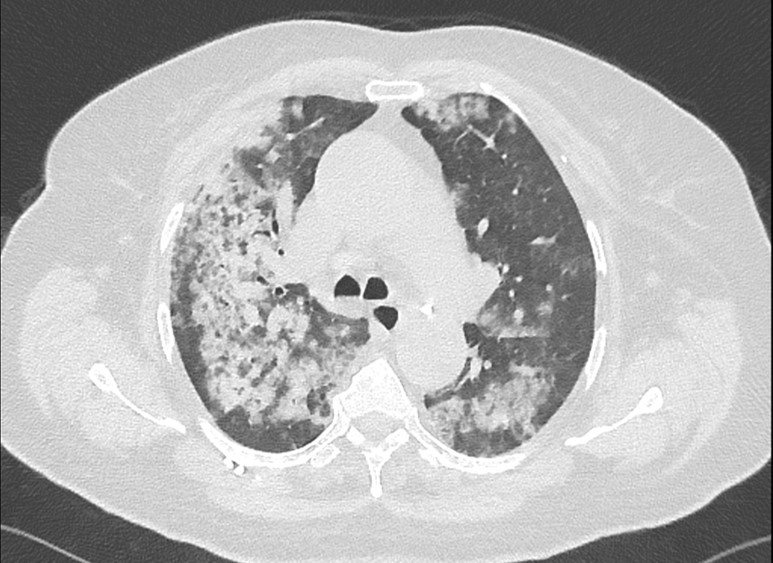

La patiente est rapidement mise sous ventilation mécanique après intubation en séquence rapide. Une radiographie thoracique est réalisée (figure 1) :

Figure 1 (source : É. Crickx)

Question 5 - Parmi les propositions suivantes, laquelle (ou lesquelles) est (sont) exacte(s) ?

La radiographie est réalisée au lit après intubation, l’index cardiothoracique n’est pas évaluable dans ces conditions. On note un syndrome alvéolaire bilatéral (opacités floconneuses) prédominant à droite.